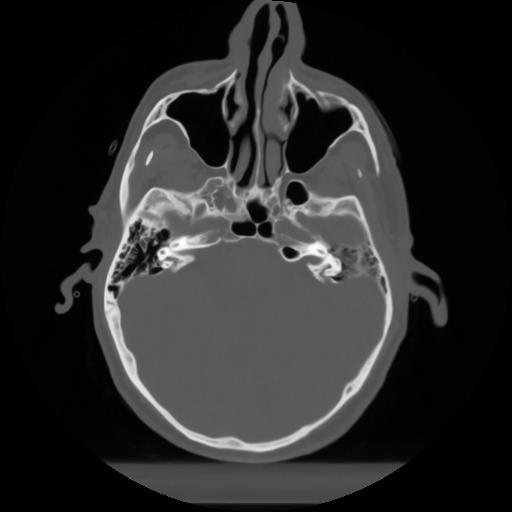

10 P.BLANDAS,,Axial,2.0,P.BLANDAS,,